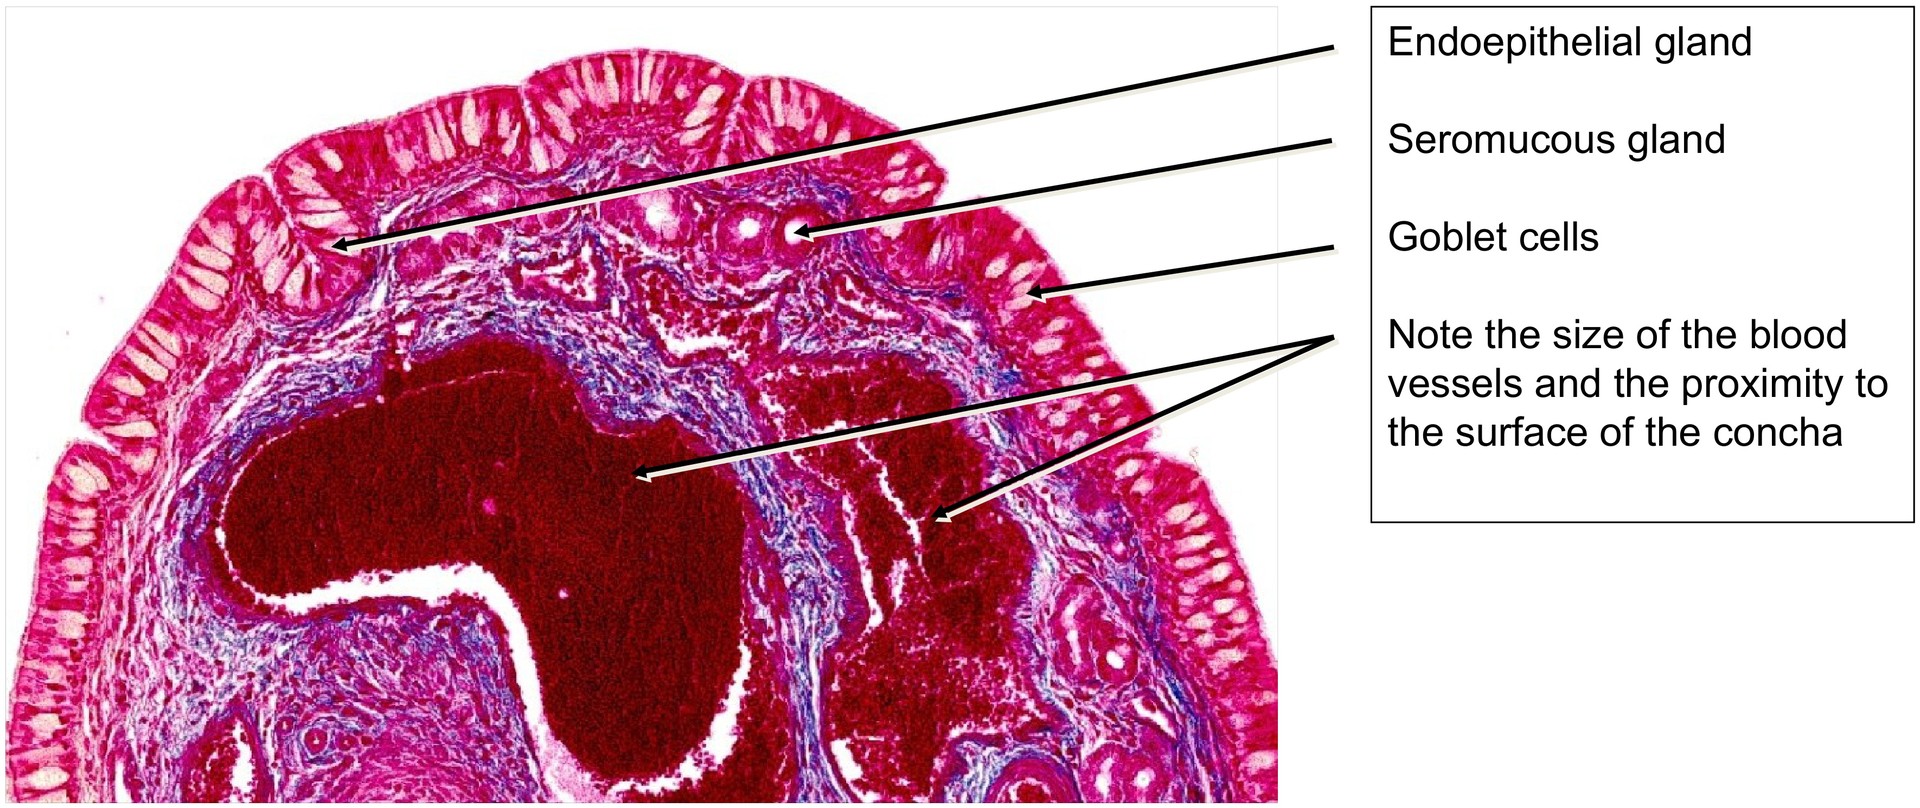

Nasal concha

The nasal concha has a bony core, and therefore this specimen was demineralized before sectioning. Azan staining colors the epithelium, erythrocytes, and mature bone in shades of red, while connective tissue appears blue.

The nasal conchae increase the surface area of the nasal cavity, thereby facilitating their functions in conditioning the inhaled air — warming, humidifying, and cleaning it — while also contributing to the creation of a largely laminar airflow. Although the conchae of sheep differ in shape from those of humans, their function and histological structure are comparable.

The surface is lined by respiratory epithelium, consisting mainly of ciliated columnar cells and goblet cells. Beneath this, numerous venous plexuses and arteriovenous anastomoses regulate blood flow through the capillary network, assisting in the warming of inhaled air. In addition, seromucous nasal glands open onto the epithelial surface, secreting both serous and mucous components that help moisten and cleanse the air.

The dense vascular plexuses located directly beneath the epithelium are responsible for warming the air but also explain the susceptibility to nosebleeds (epistaxis) in humans following trauma or inflammation. Endoepithelial glands, such as goblet cells, and clusters of goblet cells in small depressions, are also characteristic of the respiratory epithelium of the nasal concha.